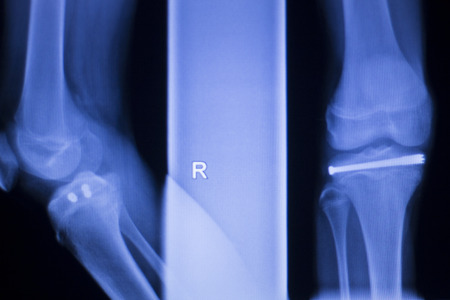

lateral view of proximal tibia fracture

x-ray image knee joint with banner design for webpage and hight quality print

X-ray of human knee joint on blue background. Medical and healthcare concept.

X-ray of human leg. X-ray image concept.

X-ray of human knees, closeup

X-ray film of a left leg

A leg xray film of a patient with an orthopedic nail in the tibia

Fused bones of the lower leg after removing the steel bonding plate, x-ray of the leg

X-ray Leg

X-ray picture showing knee joints

Knee X-ray on a black background

knee bone computer x-ray images

Knee joint implant screw xray showing in medical orthpodedic traumatology scan.

film x-ray lateral view of osteoarthritis knee patient and artificial joint with Knee Replacement.

x-ray image of both knee AP view for detect Osteoarthritis Knee or OA Knee .

X-ray picture showing knee joints (knee, bones, joint)

X-ray film of broken leg

X-ray image of Right knee Lateral view showing Total knee arthroplasty and fractures of the tibial plateau with plate and screw fixation.